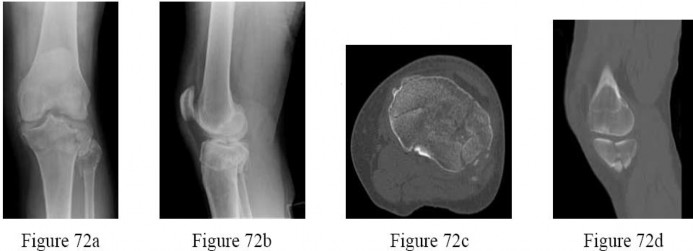

A 60-year-old male tennis player undergoes a unicompartmental knee arthroplasty (UKA) shown in Figures A and B. Which of the following statements regarding this procedure is true?

Figures A and B depict radiographs of a unicompartmental knee arthroplasty (UKA). UKA kinematics have been shown to most closely approximate native knee kinematics.

In an in vitro cadaver study, Patil et al found that TKA significantly changed knee kinematics while the unicompartmental replacement preserved normal knee kinematics.

Fisher et al performed a retrospective study comparing the short-term outcomes of small-incision unicompartmental knee arthroplasty (UKA) with standard total knee arthroplasty (TKA) in 91 consecutive patients older than 70 years. They found: 1) Blood loss was significantly more for the TKA group, as was the need for blood transfusion. 2) Patients with unicompartmental replacements had a much quicker return of function and discontinuation of pain medication. 3) While knee scores and ROM were similar preoperatively, both were better in the unicompartmental group at each postoperative time interval. 4) Narcotic use and length of hospital stay were also significantly less for the unicompartmental group. Therefore answers 2,3,4 and 5 are false.